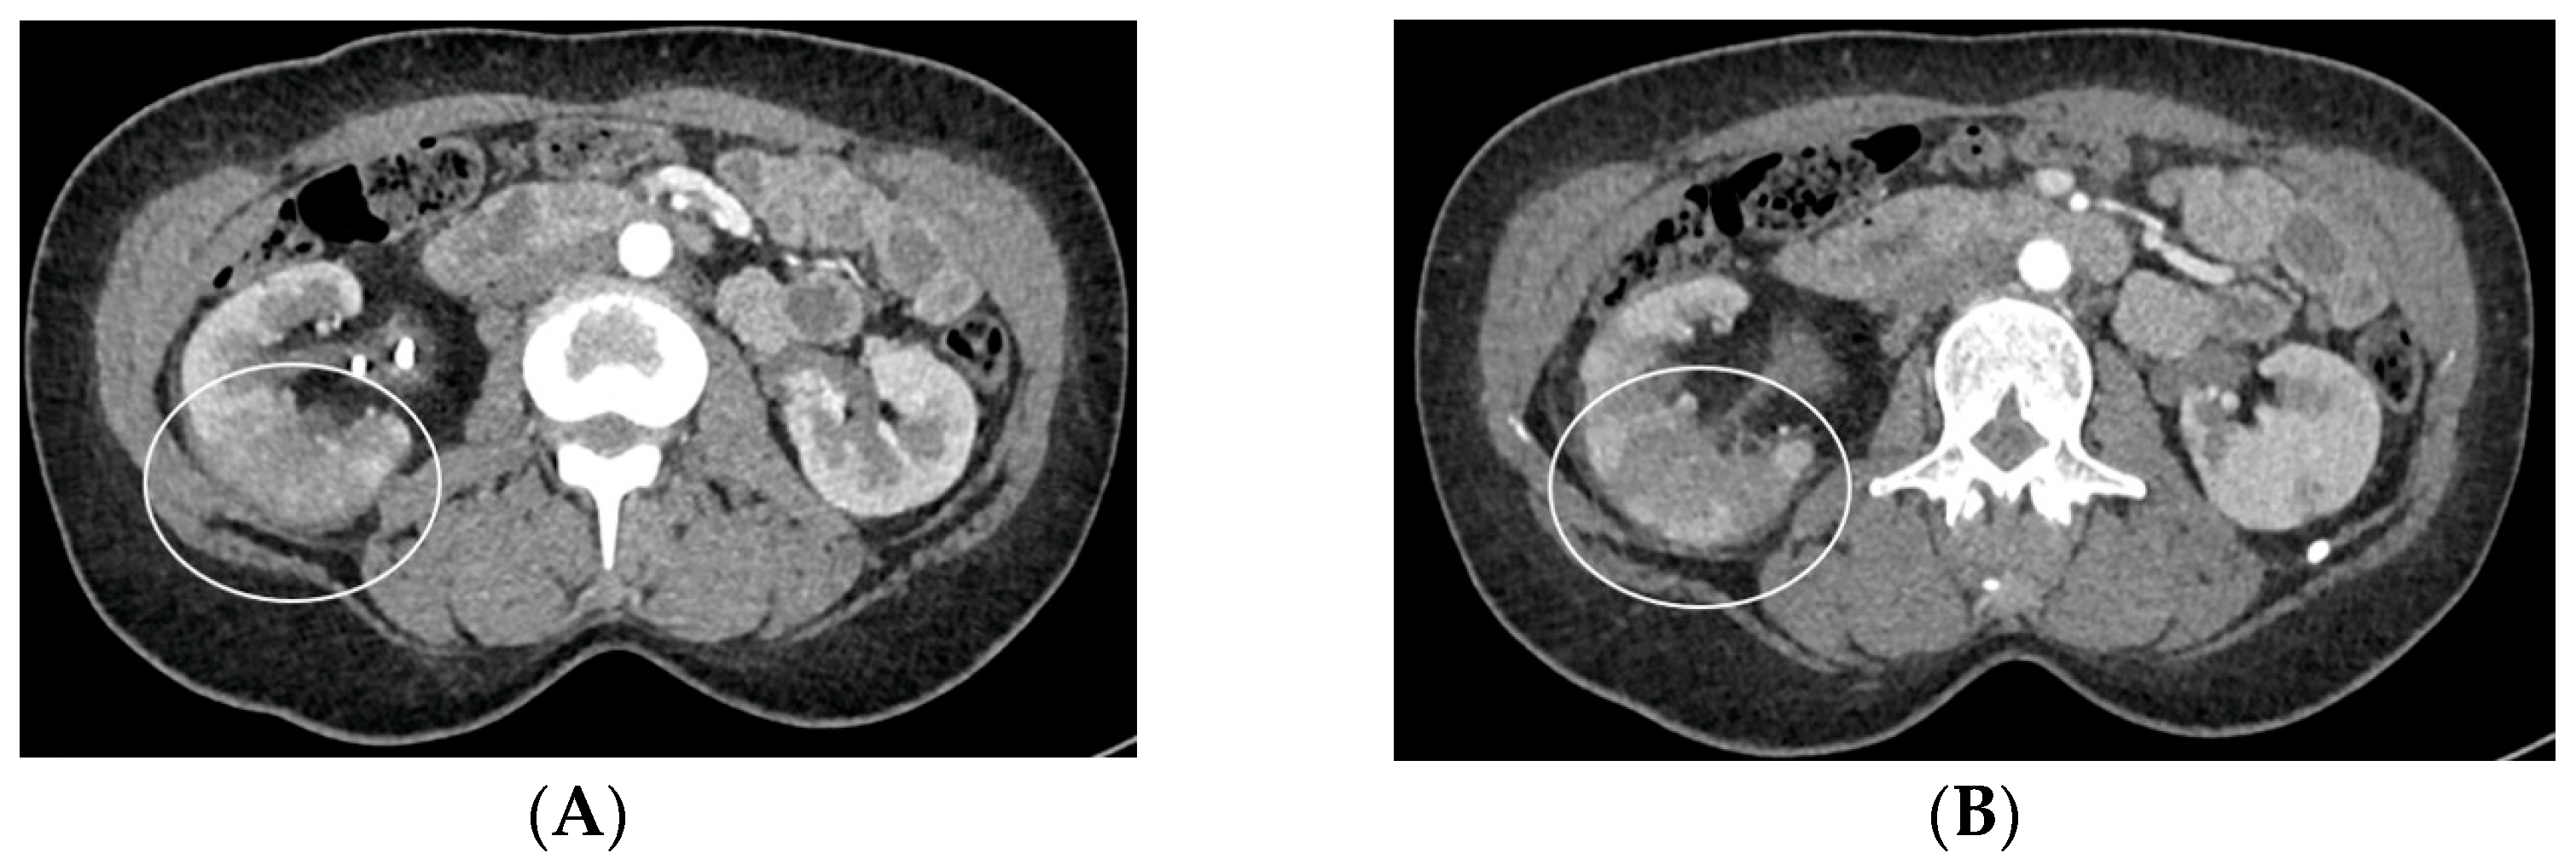

- Bleeding: The erosion of the stent into the arterial system is a rare and feared complication of ureteral stent placement, which can cause hematomas (Figure 10 and Figure 11), active bleeding, or pseudoaneurysm (Figure 12, Figure 13 and Figure 14). To avoid mortality from these complications, a high level of clinical suspicion is essential. Intermittent hematuria in a patient with a stent is typically the usual clinical scenario. However, massive hematuria and circulatory collapse can occur due to the manipulation of the ureteral stent [2,39].